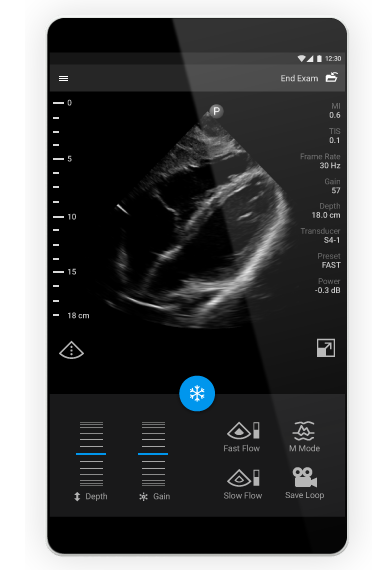

The Lumify app enhances imaging to help confidently and quickly assess MSK patients. Advanced imaging algorithms automatically adjust, creating an exceptional image. If you need to, fine-tune scans by adjusting depth, gain, power, and color through a simple and intuitive multi-touch interface.